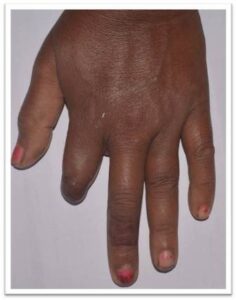

The Department of Prosthodontics and Crown & Bridge, in association with various Departments of Goa Medical College (Neurosurgery, Plastic Surgery, Surgery, Ophthalmology, and ENT), carries out complex rehabilitations of patients suffering from various developmental and acquired defects.

- Prostheses for maxillofacial defects